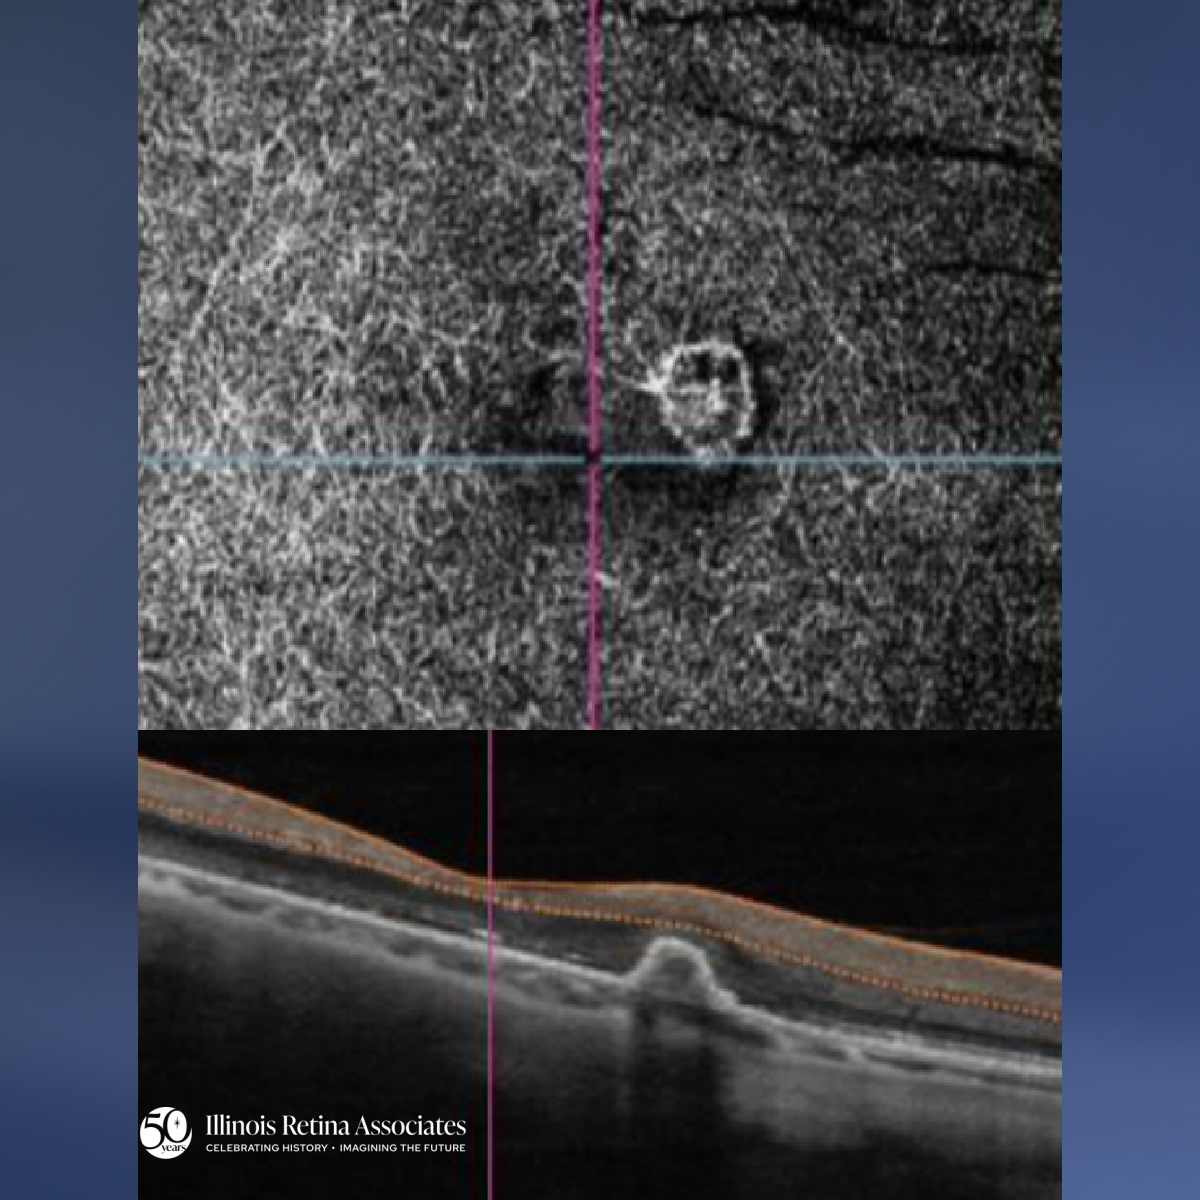

Mypopic Degeneration